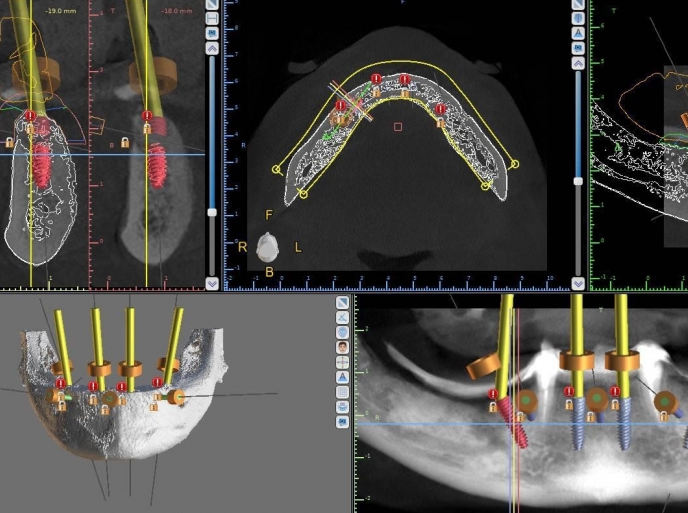

Vă prezentăm un caz All-on-4 finalizat cu succes cu ajutorul a 2 ghiduri chirurgicale realizate 100% cu ajutorul tehnologiei digitale.

Am folosit doua ghiduri: unul pentru osteoplastia crestei alveolare, iar cel de-al doilea pentru inserarea implanturilor.